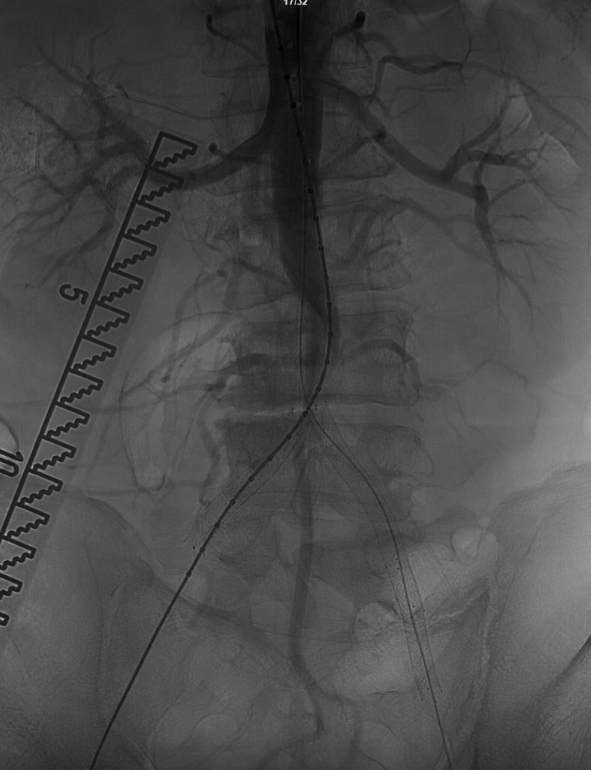

在超声引导下,成功完成双侧股总动脉穿刺。通过导管配合超滑导丝,顺利通过病变区域进入腹主动脉下段,造影明确腹主动脉下段及双侧髂动脉完全闭塞的病变范围与程度。

术前影像学评估:CTA显示腹主动脉下段闭塞,双侧髂总、髂外动脉支架内闭塞,右侧股动脉亦存在闭塞。结合急性加重病史,考虑为“基础狭窄+急性血栓形成”,不排除栓塞可能。